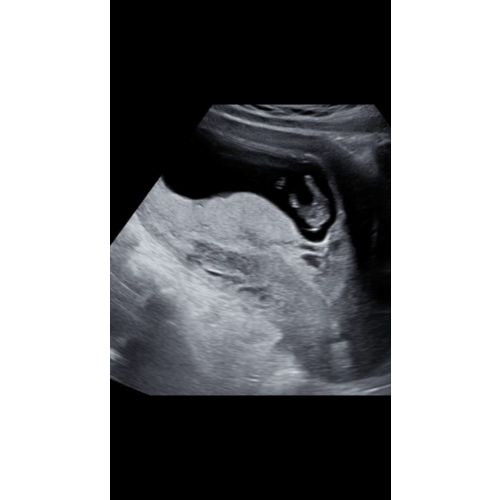

Daar ga ik wel vanuit maar weet ik niet 100% zeker. Dit was onze echo van 16/17 weken en wij krijgen een jongen. Bij een meisje zie je meestal niets zitten en een streepje

Ik heb gister bij de gynaecoloog een controle echo gehad bij 14+3 en ik dacht ik neem m'n kans en vroeg of ze kon zien wat het was. Nee zei ze dat is nog net te vroeg. Het us nu nog de nub. Vanaf week 15/16 kun je het wel zien. Het pretecho bureau bij m'n verloskundige doet ook pas geslachtsechos vanaf week 15.

Bij mij konden ze met 13 weken met zekerheid zeggen dat ik zwanger ben van een jongetje en als je goed naar de foto kijkt zie je ook echt iets zitten haha!

Je zou de nub kunnen toepassen, maar om daar meer over te zeggen heb je een foto van de zijkant nodig en niet de onderkant..